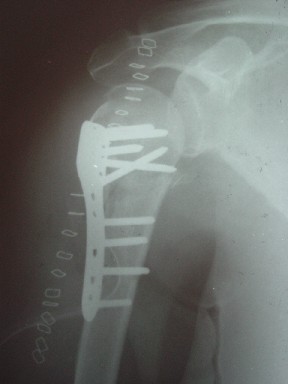

В этом плане Locking plate очень хороша так как позволяет начать движения сразу после операции.

Клинические снимки - 3 недели после операции